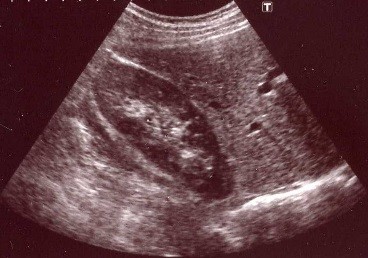

超音波検査

超音波とは、人間の耳では聞くことを目的としない、2万ヘルツ以上の高い周波数の音です。 一定方向に直進し、当たる物質によってそのはね返り方が異なる性質を利用して、画像を映し出すことができる検査です。

検査には、心臓を検査する心エコー、主に上腹部を検査する腹部エコー、首を検査する甲状腺エコー、頸動脈エコー、両足の静脈を検査する下肢静脈エコー、胸部を検査する乳腺エコーなどがあります。

腹部エコー

腹部にはたくさんの臓器がありますが、その中でも、肝臓・胆のう・膵臓・腎臓・脾臓を中心とした上腹部の臓器の形態を見ていきます。患者様の症状にあわせて、膀胱・前立腺・子宮・卵巣を見ることもあります。

超音波は空気があるとうまく画像としてとらえることができません。腹部はもともとガスが多い部位ですので、より良い状態で検査ができるように、患者様に大きく呼吸をしてもらうようにお願いしています。

また、検査当日の朝は食事を抜いていただきます。これは、胃内に食べ物が残ったり、ガスがたまったりして、肝臓などの臓器がうまく描出できなかったり、また、胆のうが小さくなり胆のうの中が見えにくくなったりするのを防ぐためです。